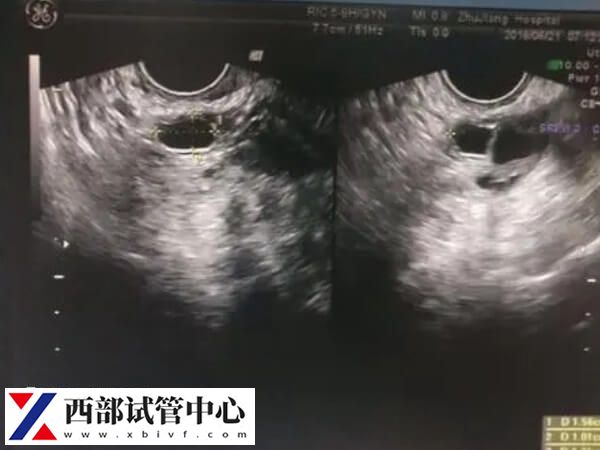

通过B超结果辅以性激素值检测,若不能正常排卵,通过激素值能初步确定排卵问题所在,为下一步治疗提供诊断依据。

3、确定卵泡数量和质量

可测出卵巢中优质卵泡量,还能测出哪个卵巢排卵,以及卵泡质量如何,以及子宫内膜是否适合孕卵着床等。